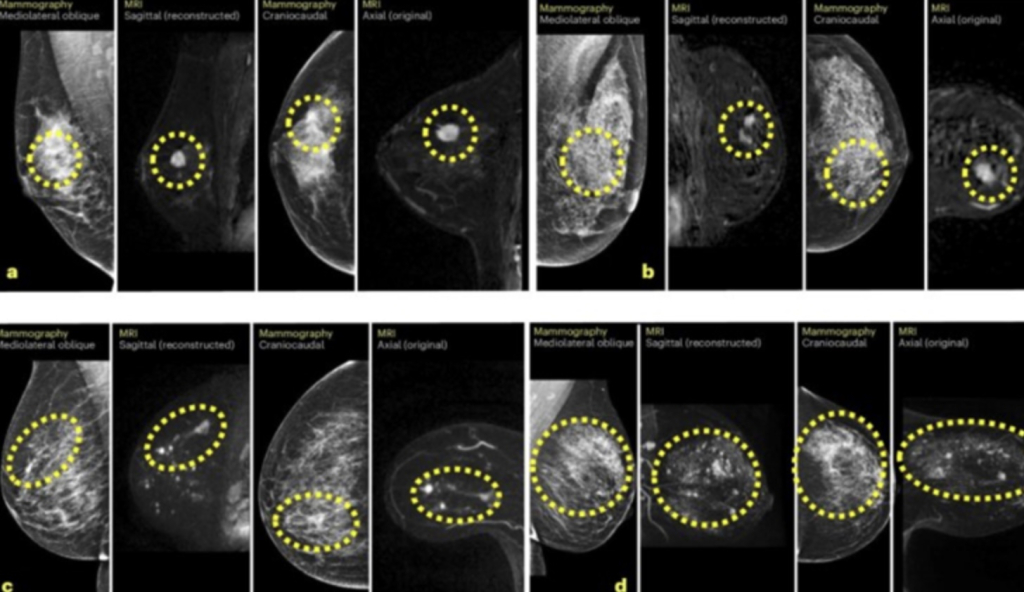

Koristeći Mirai, algoritam umjetne inteligencije utemeljen na dubokom učenju, grani strojnog učenja posebno prikladnom za rješavanje problema iz područja umjetne inteligencije, istraživači su proučili svaki mamogram da bi generirali personalizirani trogodišnji rezultat rizika na temelju gustoće dojki i suptilnih značajki snimanja nevidljivih ljudskom oku.

Model je uspješno predvidio do 42 posto svih intervalnih karcinoma među ženama koje su identificirane kao osobe koje spadaju među prvih 20 posto kada je posrijedi rizik, što je potencijalan napredak u personaliziranom probiru raka dojke.

To bi kliničarima moglo omogućiti da pacijenticama s najvećim rizikom ponude i dodatna snimanja, poput magnetske rezonancije ili mamografije s kontrastom.